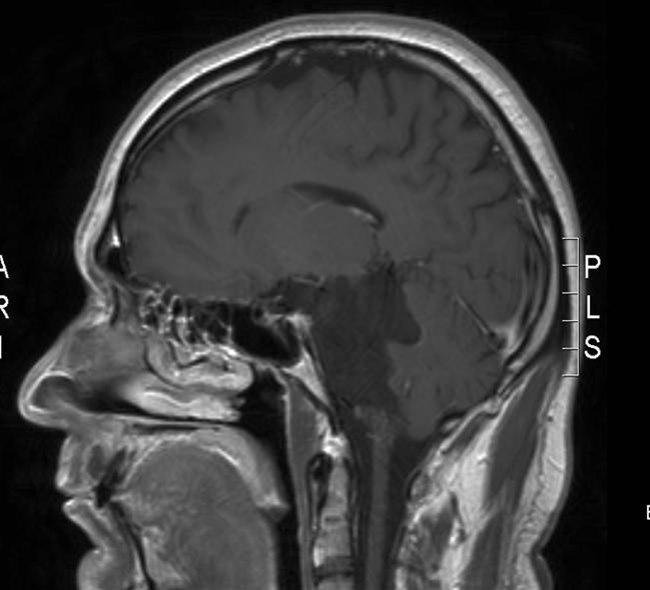

Epidermoid tumor, sagittalt snitt

Gjengitt med tillatelse av Radiologisk avdeling, Universitetssykehuset Nord-Norge